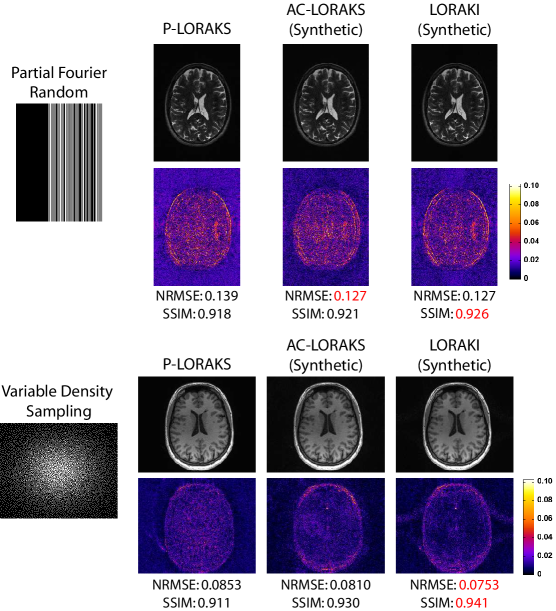

5 Discussion

The results shown in the previous section demonstrated that LORAKI has potential advantages compared to existing AA methods when sufficient ACS data is available, and also that synthetic ACS training data is potentially useful for scenarios where it may be impractical to acquire a large amount of actual ACS data. In practice, there can also be certain scenarios where no ACS training data is available, where existing calibrationless reconstruction methods like SAKE and LORAKS (which are also based on linear autoregressive modeling principles) have previously demonstrated value [8, 9, 19]. While the LORAKI formulation does not directly address calibrationless scenarios, it is worth noting that LORAKI could also potentially be applied to such scenarios if synthetic ACS data can be generated (e.g., by applying a calibrationless reconstruction method as an initial step). As an initial proof-of-principle for this idea, we performed two different calibrationless simulations, as shown in Fig.ย 7. With the T2-weighted data, we simulated calibrationless random partial Fourier undersampling with an effective acceleration factor of . With the T1-weighted data, we simulated calibrationless variable density random sampling with an effective acceleration factor of . In both cases, we used the โSโ-version of the nonconvex P-LORAKS method [19] (using publicly available software [41]) to generate an initial reconstruction. This initial reconstruction was then used as synthetic ACS training data to train LORAKI, and LORAKI reconstruction was then performed. Reconstruction results are shown in Fig.ย 7, and we also show the P-LORAKS reconstructions and AC-LORAKS reconstructions (trained using the P-LORAKS reconstruction as ACS data) for reference. As can be seen, the LORAKI reconstruction frequently has the best performance metrics compared to P-LORAKS and AC-LORAKS. The one exception is that AC-LORAKS has a slightly better NRMSE value for the T2-weighted data, although the difference in NRMSE between LORAKI and AC-LORAKS is nearly negligible in this case (i.e., an NRMSE of 0.1274 for LORAKI versus 0.1271 for AC-LORAKS). These results confirm that LORAKI-type approaches can still have relevance to calibrationless scenarios.